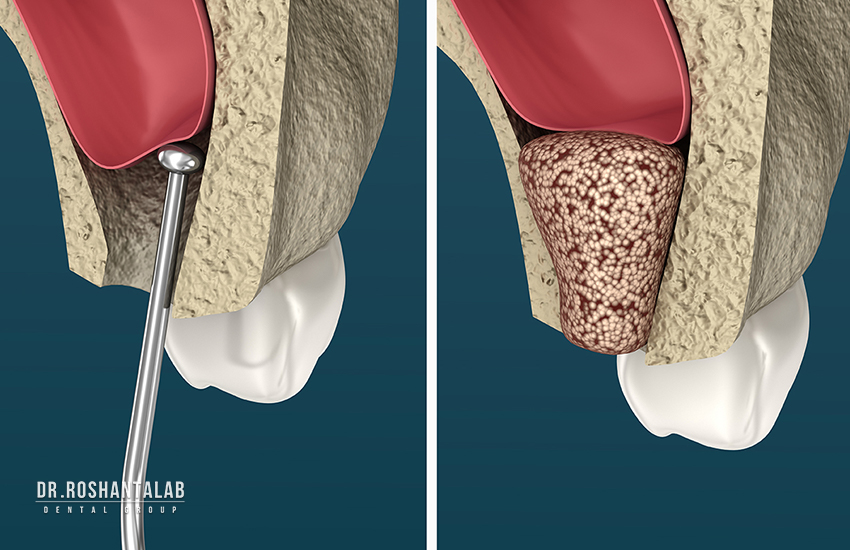

اگر استخوان فک کافی نباشد، جراحیهایی مانند سینوس لیفت یا پیوند استخوان لازم است که قیمت را افزایش میدهد. استخراج دندان، درمان عفونت لثه یا استفاده از بیهوشی نیز هزینههای جانبی اضافه میکنند.